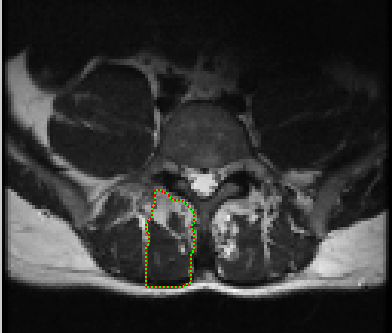

The first step is selecting the region of interest (ROI) from the MRI-defined lumbar muscles, which can be any among the erector spinae (ES) muscles, lumbar multifidus muscles (LMM) or psaos muscles, located either on the right or the left side of the spinal column [2, 5]. The user has to define the ROI by plotting a mask over the input image using livewire technique [21], as shown in Figure 2.

The livewire (or intelligent scissors) [21] is a semi-automatic image segmentation technique that allows the user to interactively select the ROI on an input image using mouse clicks along the contour of the ROI. When the user starts the selection of the ROI with a mouse click, a virtual wire is created linking the first clicked point (referred to as an anchor) to the point where the mouse is over, following a path that is as close as possible to image features detected as edges using Dijkstra’s lowest cost path algorithm. Figure 2 shows the result of a user segmentation using this tool.

The Livewire technique tends to work much slower in high resolution images, which would preclude its use. To resolve this, the input image was down sampled and the mask is defined in the low resolution image. The user defined mask is realized as a set of points in 2D coordinates, f(x,y)𝑓𝑥𝑦f(x,y). Then using the set of points f(x,y)𝑓𝑥𝑦f(x,y), the region inside the mask is cropped from the input image.

Refer to caption

Figure 2: MRI input image with user defined mask using Livewire interactive segmentation